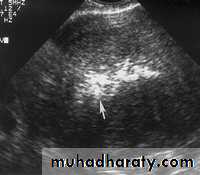

Hemorrhagic ovarian cysts:

Hemorrhagic cyst of ovary with co-existing chocolate cyst/ endometrioma:

This patient has a co-existing chocolate cyst with a hemorrhagic cyst in the same (right) ovary. The cyst on the left half of the ultrasound image is a hemorrhagic cyst. Note the fine fibrinous strands within the cyst suggesting clot formation. The cyst on the right half of the image is homogenous with fine echoes throughout the ovarian cyst. This is a typical appearance of an endometrioma (chocolate cyst)